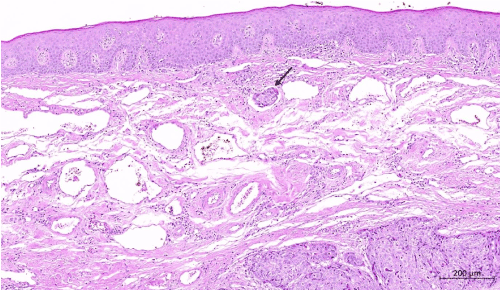

Figure 3. Tumor islands unrelated to the surface epithelium. H&E; x1

Figure 4. Tumor thrombus is seen in the lymphatic below the surface epithelium. H&E; x5